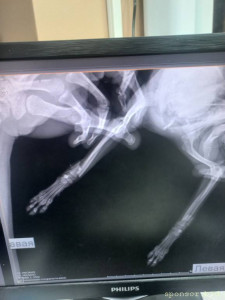

🆘🆘🆘 ПОМОГИТЕ ОПЛАТИТЬ ОПЕРАЦИЮ! Маленький той , сломала две передних лапки. Лапки просто отломленный, болтаются. Срочно нужно прооперировать🤧Стоимость такой операции 28 тыс. рублей, одна лапка 12-14 тыс ((((( Друзья, помогите поставить девочку на лапки 🙏🏻🙏🏻🙏🏻

Помогите сохранить лапки тойчику 128591; - 1682859004353.jpg

Помогите сохранить лапки тойчику 128591; - 20230419_204628.jpg

Помогите сохранить лапки тойчику 128591; - 20230419_204647.jpg

Помогите сохранить лапки тойчику 128591; - Screenshot_20230430-163919.jpg

Помогите сохранить лапки тойчику 128591; - Screenshot_20230430-163547.jpg